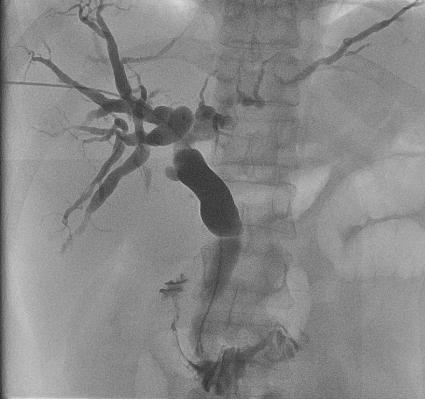

DSA引导下胆道穿刺引流

包括各类胸腹腔积液、心包积液、腹腔盆腔脓肿的穿刺抽吸置管引流。以及梗阻性黄疸时可行超声或者DSA引导下经皮经肝胆管、胆囊穿刺置管,减黄效果立竿见影,又为进一步治疗建立了“救命”通道。

4、胆道,胆管穿刺等穿刺引流术。